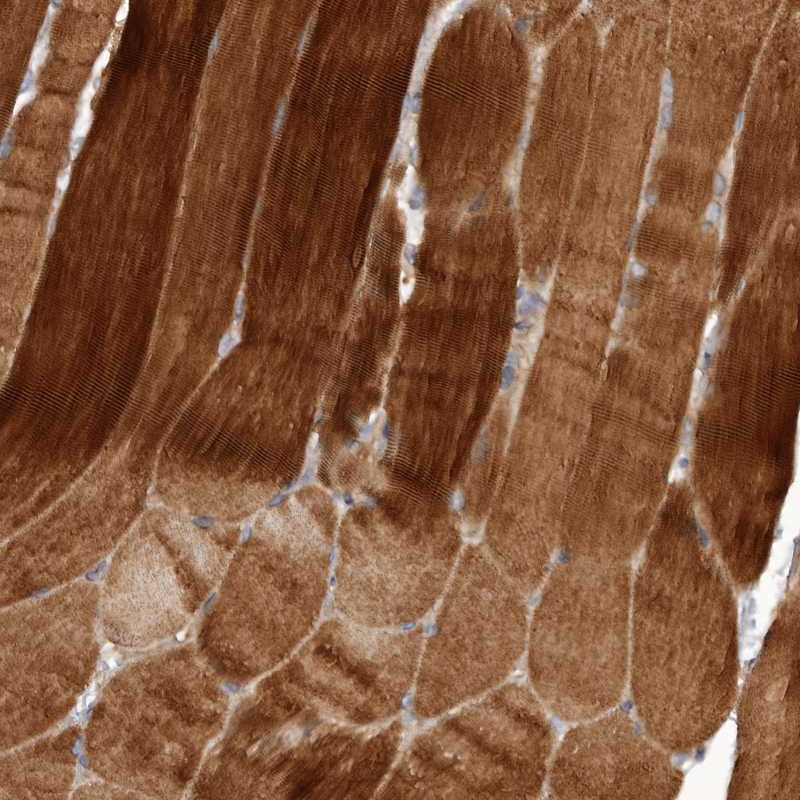

Immunohistochemical staining of human skeletal muscle shows strong cytoplasmic positivity in myocytes.